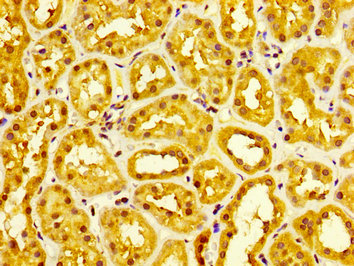

IHC image of CSB-PA822278LA01HU diluted at 1:300 and staining in paraffin-embedded human kidney tissue performed on a Leica BondTM system. After dewaxing and hydration, antigen retrieval was mediated by high pressure in a citrate buffer (pH 6.0). Section was blocked with 10% normal goat serum 30min at RT. Then primary antibody (1% BSA) was incubated at 4°C overnight. The primary is detected by a biotinylated secondary antibody and visualized using an HRP conjugated SP system.